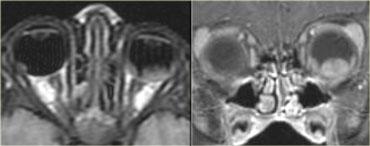

Trên hình bên trái, thần kinh thị giác bên phải có hình ảnh bình thường.

Lưu ý rằng thần kinh thị giác là một bó chất trắng.

Nó có cùng cường độ tín hiệu với chất trắng trong não.

Ở phía đối bên, thần kinh thị giác có tín hiệu tăng cao.

Đây là tổn thương ngoài nhãn cầu trong nón cơ, và chúng ta cần nghĩ đến các bệnh lý tân sinh so với bệnh lý mất myelin.

Tiếp tục xem hình ảnh tiếp theo.Bên trái là hình ảnh chuỗi xung FLAIR kết hợp kỹ thuật ức chế mỡ (fat-sat).

Lưu ý tín hiệu bất thường và thực tế là thần kinh thị giác không bị phì đại, điều này giúp loại trừ khả năng u.Hình ảnh tủy sống cổ cho thấy một đoạn dài tổn thương không chiếm chỗ.

Dựa trên các hình ảnh này, chẩn đoán phân biệt bao gồm xơ cứng rải rác (MS) và hội chứng Devic (còn gọi là viêm tủy thị thần kinh).

Do MS phổ biến hơn nhiều, đây sẽ là chẩn đoán có khả năng nhất, nhưng trường hợp này thực tế là hội chứng Devic.Một số tác giả coi hội chứng Devic là một thể của MS, tuy nhiên hội chứng Devic khác với MS ở các điểm sau: